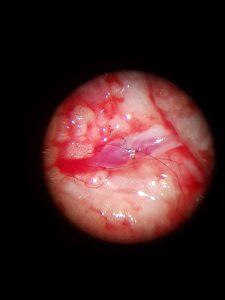

An on-ground videographer providedthe live feed from specialized audio and video equipment installed in the four operating theatres. The live feeds were sent over Microsoft Teams and broadcast using Microsoft Stream to a global audienceextending from Australia to Argentina. During the two days, live surgeries by five leading surgeons were conducted in parallel with live voiceover added to the feed to explain nuances of surgical skills and techniques.

“COVID-19 brought physical conferences to a halt, with no one being sure of the resumption of previous normalcy. Adapting to change is important to grow. At Ganga, we wondered if we could still do the popular annual livehand operative course. Instead of telecasting to our own auditorium, Microsoft Teams enabled us to telecast it to the world. Around 20 hours of surgical demonstration was possible every day and we were able to demonstrate 21 procedures. Microsoft Teams’ high definition streaming was flawless, enabling surgeons view structures less than a mm in size, even better than being at Coimbatore. We were impressed by the capability of the product and the passion of the support team at Quadra, who really helped us to reach out,” said Dr. S Raja Sabapathy, Chairman of the Department of Plastic Surgery,Ganga Medical Centre & Hospital.